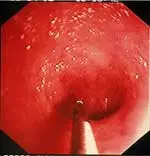

Compared to other alimentary tract organs, the duodenal mucosa has a more granular texture, due to its prominent villous architecture. Duodenal and jejunal mucosa color varies from pale pink to tan in animals having recent biliary secretion. Submucosal lymphoid aggregates appear as oval, slightly depressed mucosal structures present along the descending duodenum (in dogs) and should not be interpreted as mucosal lesions. Other normal mucosal structures include the major duodenal papillae (present in the dog and cat) and minor duodenal papillae (present only in the dog) (Figure 1).

The best biopsies are obtained by directing the instrument at a 90° angle (perpendicular) to the mucosal surface at flexure locations (A). (Note the numerous white spots along the mucosa, which are areas of light reflection, not lymphangiectasia.) Flexure sites facilitate targeted, deep mucosal tissue purchases while reducing the tendency of the forceps cups to slide along the superficial mucosa. Tissue biopsies procured at nonflexure sites will require directing the endoscope tip (and biopsy forceps) obliquely toward the mucosa.